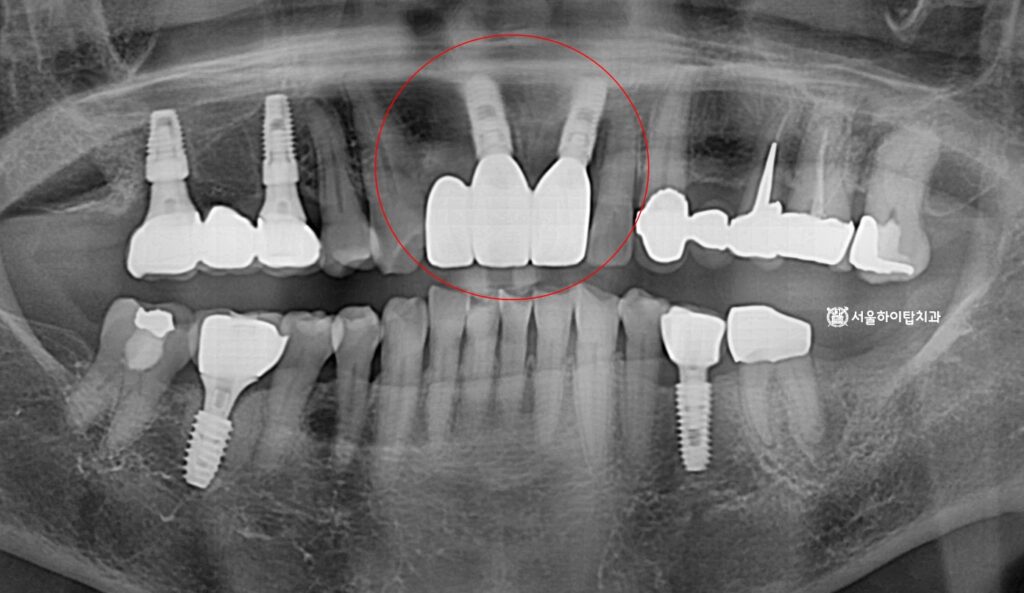

2. 정밀한 CT 모의 식립

현재는 치관이 완전히 파절된 상태이며,

치조골 소실이 동반되어 있습니다.

따라서 보존적 치료만으로는

장기 예후를 기대하기 어렵습니다.

이러한 경우에는 발치 후

골 재생 및 임플란트를 계획하는 것이

기능, 심미 회복 측면에서

합리적인 접근입니다.

이에 따라, 픽스처가 심어질 위치를

앞선 CT를 통해 사전에 확인하고,

잔존골의 높이, 밀도, 두께 등을

면밀하게 분석합니다.

3. 수술 완료

시뮬레이션에 따라

정확한 위치이 안전하게

픽스처각 심겨진 모습입니다.

사진을 보면 두 개의 픽스처만

식립된 것을 확인할 수 있는데,

이는 전치부에 해부학적 구조와

골 형태를 고려한 결과입니다.

치조골 폭이 좁고, 치은라인이

중요한 부위이기 때문에

불필요하게 많은 임플란트를 심기보다는

기능 안정성과 심미 조화를 동시에

확보할 수 있는 최소 개수를

선택하는 것이 원칙입니다.

만수동 치과 에서 남은 한 자리는

폰틱(가짜치아)으로

대체될 것으로 보입니다.